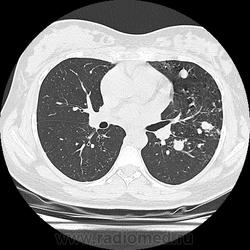

- https://radiomed.ru/sites/default/files/styles/case_slider_image/public/user/19376/img-0001-00042.jpg?itok=2lfc8wWs

- https://radiomed.ru/sites/default/files/styles/case_slider_image/public/user/19376/img-0001-00052.jpg?itok=YRoMhMgw

- https://radiomed.ru/sites/default/files/styles/case_slider_image/public/user/19376/img-0001-00056_0.jpg?itok=nxleffCp

- https://radiomed.ru/sites/default/files/styles/case_slider_image/public/user/19376/img-0001-00061.jpg?itok=rsGqsfJo

- https://radiomed.ru/sites/default/files/styles/case_slider_image/public/user/19376/img-0001-00066.jpg?itok=jCurkizB

В том то и дело, что анамнез скудный, жалоб нет или врала, жила себе поживала девушка, забеременела, родила, а в правом легком "дырка".

Что касается женщины, то она не "врала". Беременность в данном случае была для неё, как лечебный pneumoperitoneum.